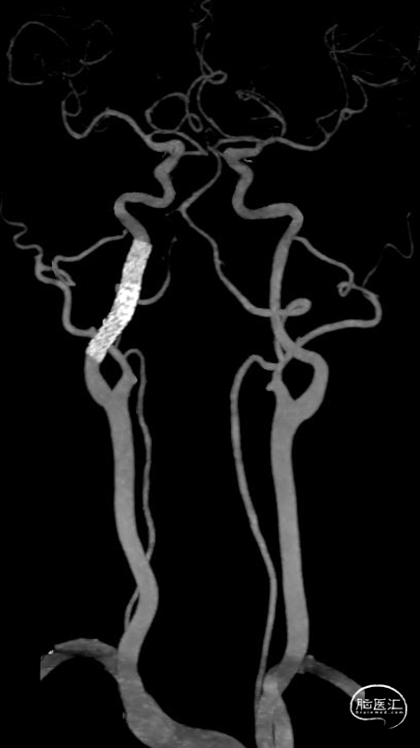

术后三个月随访:mRS 0分,颈部血管CTA显示支架形态良好。